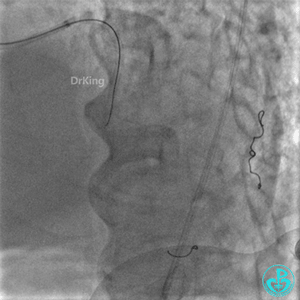

左股入路JR 4.0指引导管翻山造影,右侧股动脉穿刺点局部造影剂外漏。

明胶在血管怎么降解并发症丨前降支CTO同侧逆向开通时侧支血管破裂,弹簧圈联合明胶海绵封堵_https://www.jmylbn.com_新闻资讯_第41张

翻山5.0×8mm球囊局部封堵破口处加术者用手局部压迫。

球囊封堵30分钟后造影,破口局部无渗漏,下台观察。